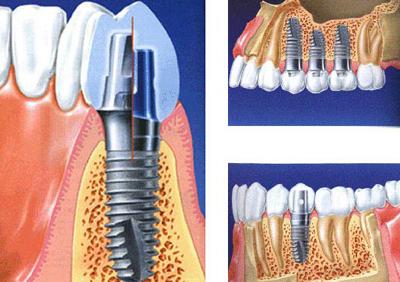

为了解决牙龈萎缩带来的问题,种植牙成为了一种常见的治疗方法。种植牙是将人工牙根植入牙槽骨中,然后再安装上牙冠,以取代缺失的牙齿。它不仅能够解决牙龈萎缩带来的影响,还能够恢复咀嚼功能和美观。